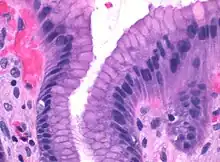

![]() Microscopic section of gastric mucosa. Foveolar cells can be seen at top of the image lining the surface and pits | |

Foveolar cells or surface mucous cells are mucus-producing cells which cover the inside of the stomach, protecting it from the corrosive nature of gastric acid.[1][a] These cells line the gastric mucosa and the gastric pits. Mucous neck cells are found in the necks of the gastric glands. The mucus-secreting cells of the stomach can be distinguished histologically from the intestinal goblet cells, another type of mucus-secreting cell.

Foveolar cells line the surface of the stomach and the gastric pits. They constitute a simple columnar epithelium, as they form a single layer of cells and are taller than their width. Other mucus-secreting cells are the mucous neck cells in the necks of the gastric glands.[2]: 257

Surface mucous cells have large quantities of mucin granules in their apical (top) surface and project short microvilli into the lumen of the stomach.[2]: 257 Mucins are large glycoproteins that give the mucus its gel-like properties.[3] As mucins are lost during routine histology preparation, they stain pale, but if preserved correctly the cells stain strongly with special techniques like PAS or toluidine blue, the last representing the anionic nature of foveolar cell secretions. Below the mucin granules, surface mucous cells have a Golgi apparatus, the nucleus, and small amounts of rough endoplasmic reticulum.[4]: 577 Mucous neck cells are located within gastric glands. These are shorter than their surface counterpart and contain lesser quantities of mucin granules in their apical surface.[4]: 578